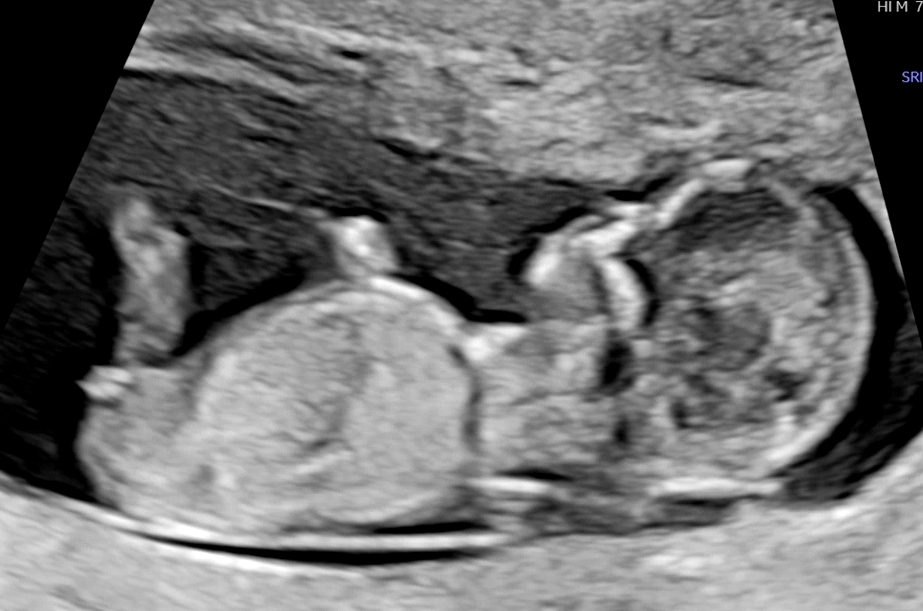

12주 각도법으로 성별봐주세요~

각도법으로 성별 투표해주세요~